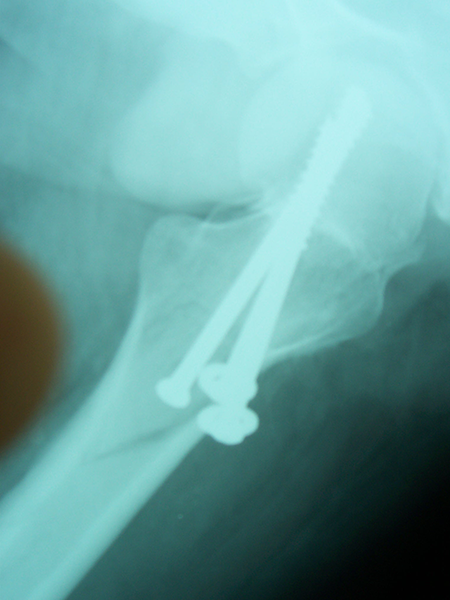

Case:7 Fracture Neck Femur with Implant failure and Re-Fixation with hemi-arthroplasty

Alcoholic Gardener by profession had slipped in bathroom & fell. He sustained fracture neck femur.He was operated with closed reduction & CC Screw fixation under IITV. Two weeks’ post fixation he again fell & sustained fracture in sub trochanteric region. He was treated with Hem-Arthroplasty with Tension band wiring.

Post Fall

Oblique-Post Fall

Lat-Post Fall